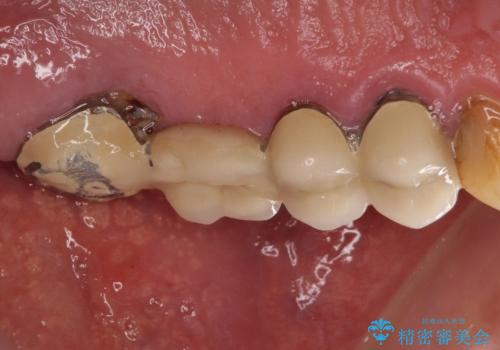

抜歯が必要な左右の奥歯 ブリッジとインプラントによる奥歯の補綴治療

- 咬んだときに奥歯に痛みを感じるとのことで来院された患者様です。

診査の結果、左側は奥歯2本、右側は1本の抜歯が必要であることが分かりました。

左側は大臼歯2本と小臼歯1本が欠損しているため、インプラント2本を治療したブリッジ、右側は中間欠損であり、前後の歯も加療が必要であったためブリッジによる補綴治療を行うこととしました。

抜歯となった歯は全て神経が抜かれた歯であり、強大な咬合力によって破折したことが原因で抜歯となりました。